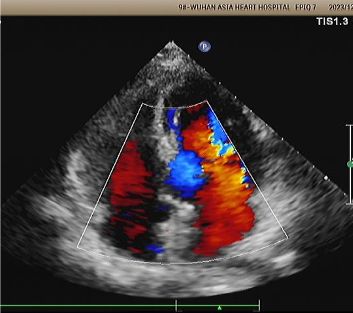

Diagnosis: Positive bubble study.

Implant: 2424 MemoSorb® biodegradable PFO occluder deployed under echo and DSA guidance.

Day 1 to 9 Months:

No residual shunt observed.

Gradual reduction in device echogenicity.